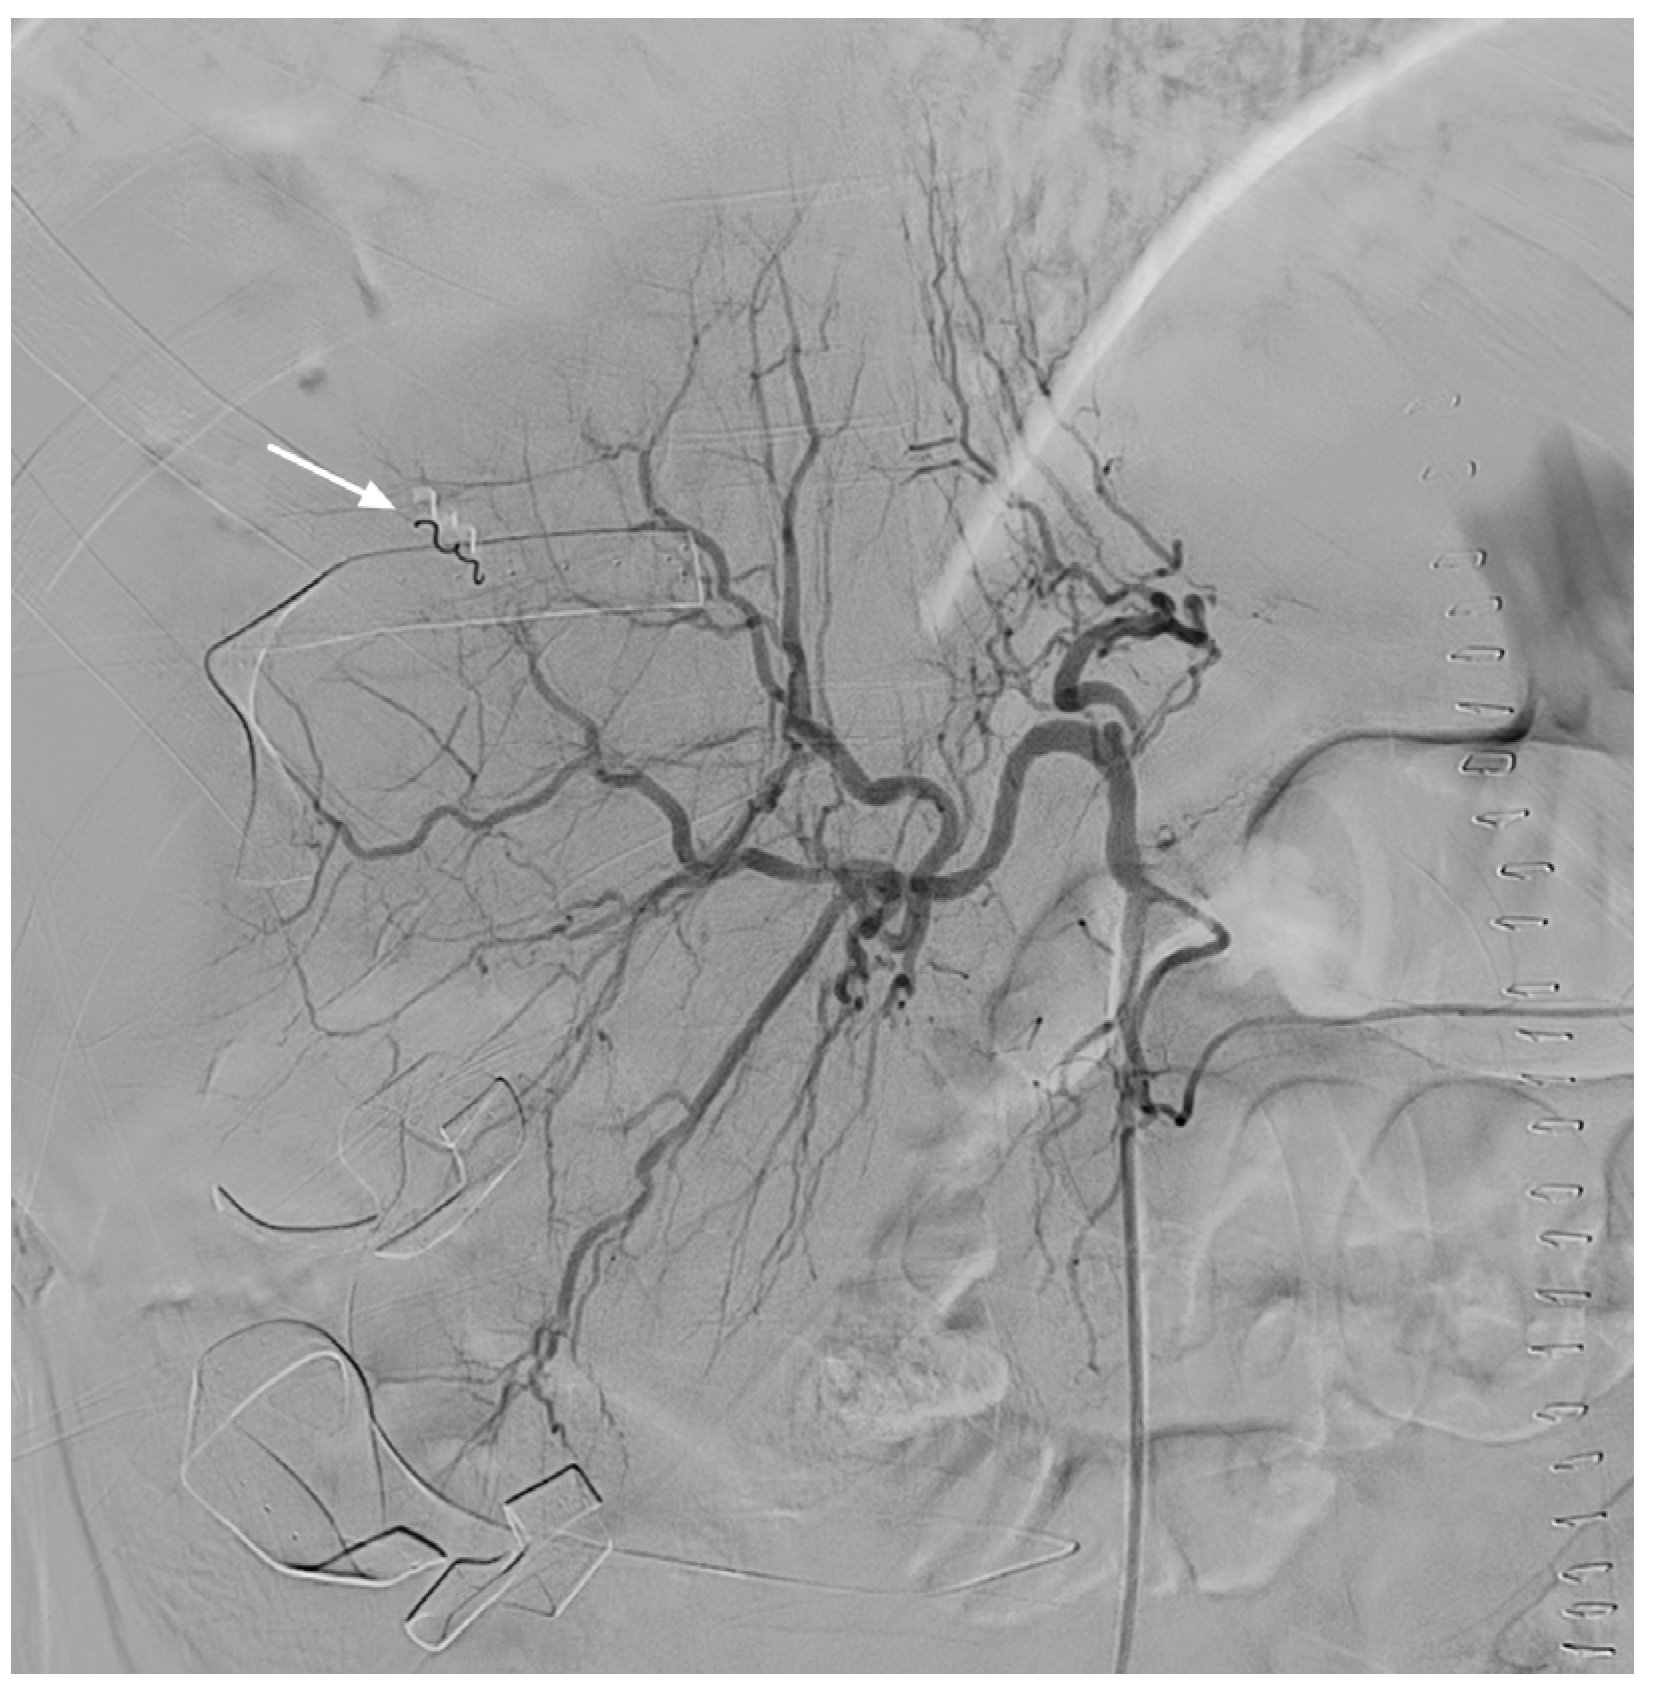

2. Case Presentation